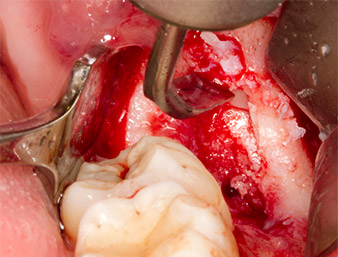

To obtain autogenous material for subsequent wound treatment, healthy bone chips were harvested from the surroundings of the root remnant with a piezo surgical instrument (Piezomed B5) (Fig. 5).

Piezomed B5

Fig. 5: Bone in the region of the alveole is lifted with a chisel-shaped piezo surgical instrument (Piezomed B5). This bone is used as autologous augmentation material after removal of the root remnant (cf. Fig. 13 and 14).

The autogenous tissue was removed with the scraper-shaped section of the working part of the instrument and stored in a physiological saline solution until further use (cf. Fig. 13).